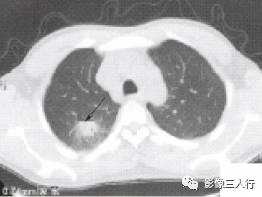

空泡征在CT及HRCT上表现为孤立结节中夹有小的低密度透亮泡影,多呈圆形、卵 圆或小条状影,形态不规则,轮廓清晰或隐约可见,其直径<5mm,可单发或多发。空泡 征形态多种多样,一个或多个,边界尚清,多个者呈蜂窝状。大者似小囊样,散在分布。有 的融合为梅花瓣样,直径>20mm。有的如细小蜂窝样,位于肿块中心,内侧缘均有细线样 光滑的壁,如纤维壁,未见细小壁结节。见图2。

(a)右上叶后段结节内见单个空泡征(肺腺癌)(b)右下叶结节内见单个空泡征(肺腺癌)

(c)右下叶肿块影内见细小蜂窝样空泡征(肺腺癌)